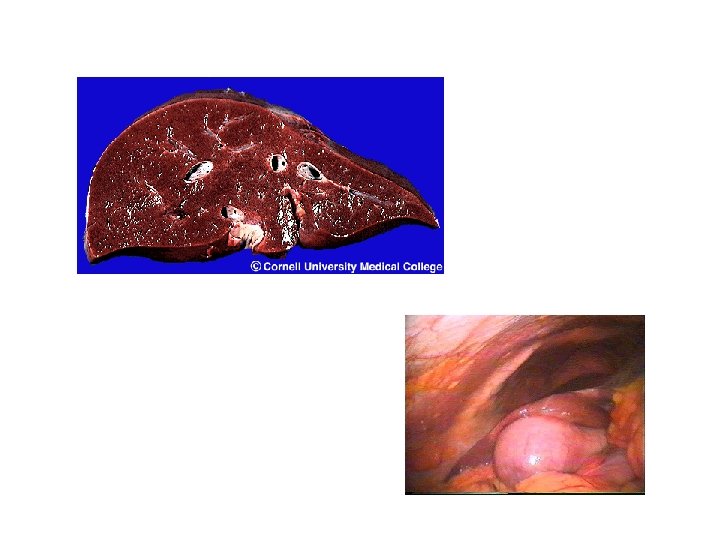

Lever, galleveier, galleblære l Leverens funskjoner: – – l Omformer og inaktiverer hormoner, giftstoffer o. l så de kan skilles ut i urin og galle. Produserer plasmaproteiner, koagulasjonsfaktorer, kolesterol Produserer og skiller ut galle. Det viktigste organet når det gjelder behandling av næringsstoffene etter at de er absorbert fra tarmen (fjerner eller tilfører blodet glukose etter behov). Gallens funksjon: – Nødvendig for spalting og absorpsjon av fett. Fettet emulgeres (dannes mindre fettdråper), gallesaltene danner miceller som transporterer fettet fra fettdråpene til tarmepitelet. Leverporten V. porta

Galleveier: l l Gallestein (Cholelithiasis): Hyppig forekommende, oftest symptomfrie. Oftest i galleblæren, men kan komme i ekstrahepatiske galleganger (Choledocholithiasis). Kan gi diffuse magesmerter, anfall med kolikksmerter under høyre costalbue, kvalme, brekning, fettintoleranse, evt. ikterus hvis beliggende i gallegang. Cholecystitt: Betennelse i galleblærens vegg. Fare ved spredning til intrahepatiske galleganger (cholangitt).

Hepatitt og toksisk leverskade l Hepatitter – – l Toksisk leverskade – – l Infeksiøs hepatitt – viktigste årsak til betennelser i leveren. Hepatitt A, B, C, D, E. B- og C-virus kan gi kronisk hepatitt. Autoimmun hepatitt. Alkohol: Kan gi fettlever, hepatitt Paracetamolforgiftning Levercirrhose – – Skyldes alkoholmisbruk og kronisk aktiv hepatitt. Fører til nedsatt leverfunksjon og portal hypertensjon med fare for øsofagusvariser og ascites. Økt risiko for leverkreft.